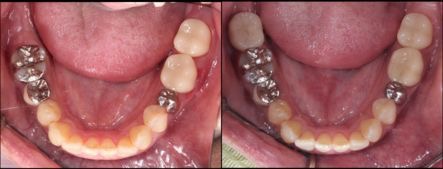

右下1本インプラント埋入した症例

全顎的にインプラント治療を行った症例